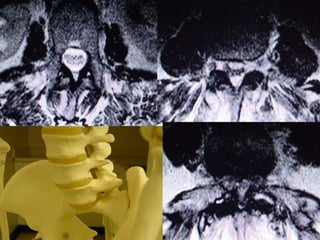

Cauda Equina Syndrome